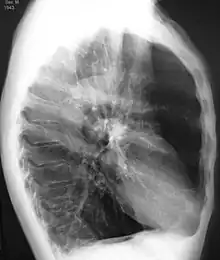

A realização de uma radiografia ao tórax e de um hemograma permitem excluir outras condições no momento do diagnóstico.[69] Os sinais característicos da DPOC observáveis em radiografia são pulmões sobre-expandidos, diafragma achatado e espaço retroesternal aumentado. Ao mesmo tempo, a radiografia permite excluir outras doenças pulmonares, como pneumonia, edema pulmonar ou pneumotórax.[70] Uma tomografia axial computorizada ao tórax permite mostrar a distribuição do enfisema pelos pulmões e pode ajudar a excluir outras doenças pulmonares.[18] No entanto, a não ser nos casos em que se planeie a realização de uma cirurgia, esta distribuição raramente influencia o tratamento.[18] Pode ainda ser realizada uma gasometria arterial para determinar a necessidade de oxigénio suplementar. Este exame é recomendado em pessoas com VEF1 inferior a 35% do previsto, com saturação periférica de oxigénio inferior a 92% e pessoas com sintomas de insuficiência cardíaca congestiva.[17] Em regiões do mundo onde é comum a deficiência de alfa-1 antitripsina, as pessoas com DPOC devem considerar a realização deste exame, sobretudo aquelas com idade inferior a 45 anos e em que o enfisema afeta a parte inferior dos pulmões.[17]

Radiografia torácica de DPOC grave, em que se observa o tamanho relativamente pequeno do coração em relação aos pulmões.

Radiografia torácica lateral de pessoa com enfisema, em que se observa tórax em tonel e diafragma achatado.